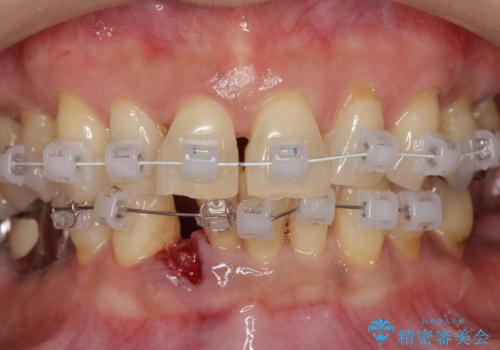

- 下顎前歯のグラつきがどんどん悪くなり、痛くて噛めなくなってきたことの改善を希望され来院されました。

下顎前歯の1本は前歯よりも前に出てしまい後ろからの力を受けることで、周囲の骨も吸収しグラつきも大きくみられます。

通常 抜歯後はインプラントやブリッジといった方法で欠損部位の機能や審美性を回復しますが、今回は臨在する歯のガタつきも利用し上下の歯を矯正治療することで人工物を装着することなく歯を並べます。